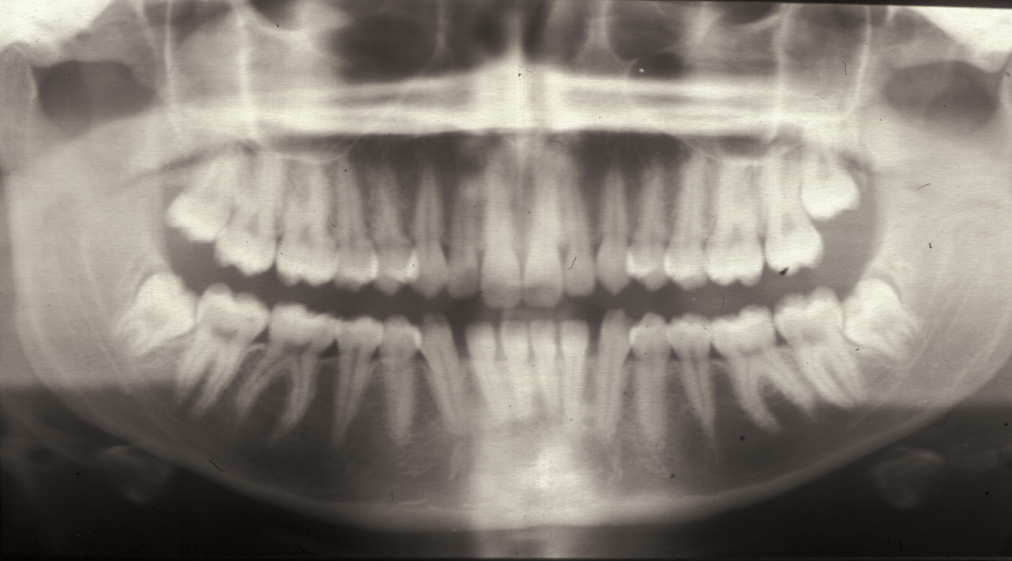

Dental panoramic radiograph (DPT)

One of the most commonly used X-ray examinations for oral and maxillofacial conditions is the dental panoramic radiograph (DPT), a panoramic X-ray image of the upper and lower jaws and teeth.

In practice, these panoramic images do show projection artefacts and ghost images, and there is a shadow from the cervical (neck) spine. It is important to remember that a two-dimensional representation / projection of a three-dimensional object will never be a perfect representation. Overall, a DPT does not provide highly defined local detail but gives a very good overview with a relatively low exposure to X-ray radiation– in many practical situations very highly resolved local detail is not required anyway. Panoramic radiographs can also be obtained for people suffering from trismus or from a particularly active gagging reflex, both making the recording of intraoral radiographs difficult or impossible. Figure 2 shows an example of a panoramic radiograph.

Figure 2: Dental panoramic radiograph (DPT) showing impacted third molars.